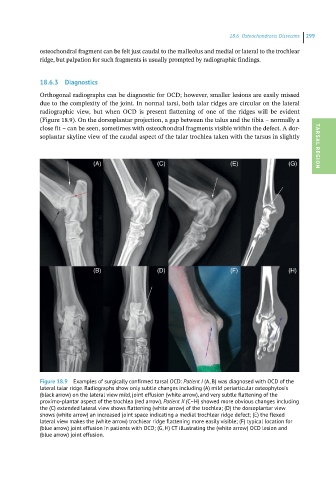

Orthogonal radiographs can be diagnostic for OCD; however, smaller lesions are easily missed

due to the complexity of the joint. In normal tarsi, both talar ridges are circular on the lateral

radiographic view, but when OCD is present flattening of one of the ridges will be evident

(Figure 18.9). On the dorsoplantar projection, a gap between the talus and the tibia – normally a

close fit – can be seen, sometimes with osteochondral fragments visible within the defect. A dor-

soplantar skyline view of the caudal aspect of the talar trochlea taken with the tarsus in slightly TARSAL REGION

Figure 18.9 Examples of surgically confirmed tarsal OCD: Patient I (A, B) was diagnosed with OCD of the

lateral talar ridge. Radiographs show only subtle changes including (A) mild periarticular osteophytosis

(black arrow) on the lateral view mild, joint effusion (white arrow), and very subtle flattening of the

proximo-plantar aspect of the trochlea (red arrow). Patient II (C–H) showed more obvious changes including

the (C) extended lateral view shows flattening (white arrow) of the trochlea; (D) the dorsoplantar view

shows (white arrow) an increased joint space indicating a medial trochlear ridge defect; (E) the flexed

lateral view makes the (white arrow) trochlear ridge flattening more easily visible; (F) typical location for

(blue arrow) joint effusion in patients with OCD; (G, H) CT illustrating the (white arrow) OCD lesion and

(blue arrow) joint effusion.